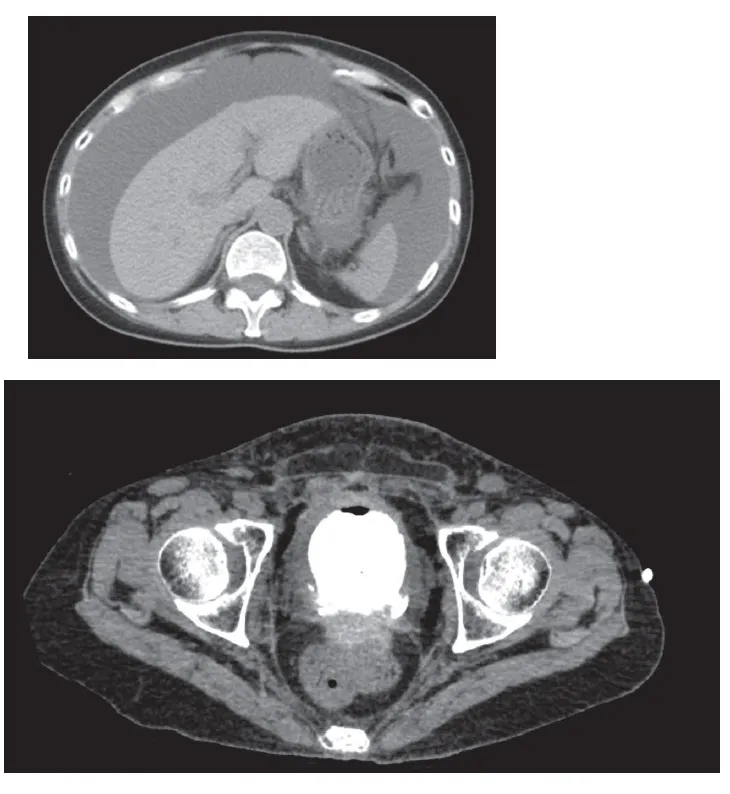

Pseudo-IRA em uma paciente com Ascite

Valkercyo Feitosa